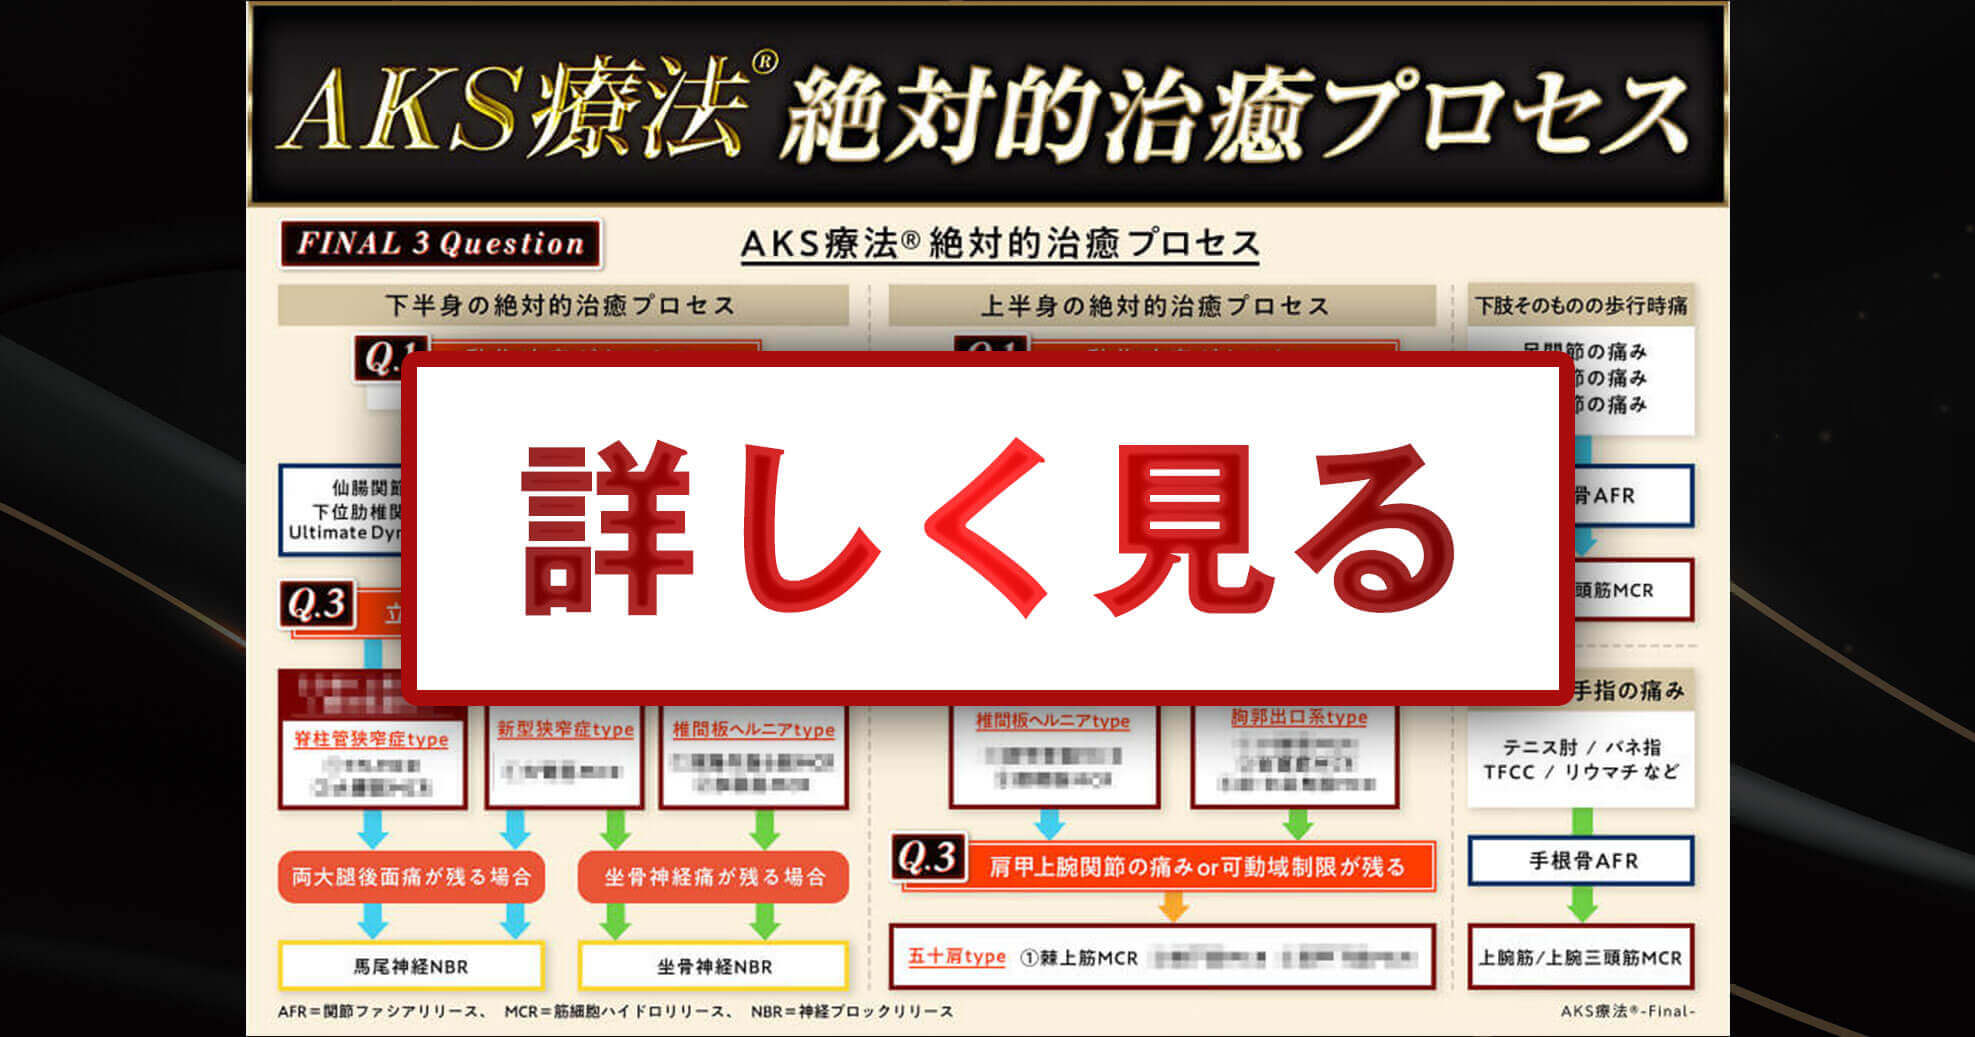

これが、AKS療法®の絶対的治癒プロセスです。この図は患者さんが来た時の問診時に使えるフローチャートになっており、あなたは上半身、下半身それぞれに対応する3つの質問「Final 3 Qestion」を患者さんに聞き、絶対的治癒プロセスに則ってチャートを進むだけで、原因が明確になり、アプローチする手技が明確になるのです。

手術宣告された重症患者さんを改善させるために

あなたがやることはたったこれだけ!

- ①フローチャートに沿って誰でも出来る3つの質問をする

⇒医師も分からない真の症状の原因が浮き彫りに! - ②チャートから導き出された手技をやるだけ

(手技自体は非常にかんたんなのでご安心ください)

かんたん2ステップでどんな重症患者さんも

改善できるようになったらいかがでしょうか?

この絶対的治癒プロセスを使えば、たとえあなたが解剖学をまったく知らない素人だとしても、患者さんの痛みの真の原因が分かるようになるので、原因が分からずに全身を揉んでみたり、治療に悩んだり不安になることがなくなるのです。

実際に私もこのプロセスを使って患者さんの問診を行ったからこそ、原因が明確になり、患者さんを回復に導くことが出来たのです。

つまり、この絶対的治癒プロセスはゴッドハンドと同じ診立てや問診、治療計画を立てるためのカンニングペーパーのようなものであり、手技の使い方をナビゲートしてくれるものです。

日常生活もままならない激痛を

2週間以内に回復させる

関節ファシアリリース

痛みの8割以上の根本原因である、関節やファシアに多く存在する、感覚センサー=固有受容器にアプローチし、ざっくりと2.5秒の触る程度でセンサーを再起動させるAKS療法®のメインテクニックです。

たった1回の施術で2週間以内に手術宣告された重症患者さんの日常生活を取り戻すことが出来、あまりに簡単&短時間で改善するので、ちょちょっと触られただけなのに大きく変化した患者さんは思わず「えっ!?」とビックリすること間違いナシ。「先生、今何をしたんですか…!?魔法みたい!」と興味津々であなたの施術に興奮する方が続出するでしょう。

レントゲンにもMRIにも映らない

根本原因を改善する

筋細胞ハイドロリリース

関節ファシアリリースで痛みの8割は改善し、日常生活もままならないほどの動作時痛は2週間で回復に向かいますが、2週間後には残りの2割の問題が浮かび上がってきます。

それが、筋肉を構成する最小単位である「筋細胞」同士が絡まり合い固まった「spasm(スパズム)」の問題です。

人体の一番深部に眠る従来の筋筋膜系の手技では到達できなかったミクロな部分にアプローチして、筋細胞同士の絡まりを1本1本パラパラにほぐし、使いやすく再構築するのが、AKS療法®の「筋細胞ハイドロリリース」なのです。

どこに行っても取り切れない痛み

しびれを消失させる

神経ブロックリリース

Final 3 Questionを使い、絶対的治癒プロセスを辿れば、素人でも症状の原因が分かり、手術宣告された重症患者さんのほとんどを回復に導けます。

しかし、約5%の患者さんは、わずかに残るしびれや神経痛を訴えます。あなたも痛みは取りきれたけど、しびれが取り切れない…という経験があるのではないでしょうか。従来のAKS療法®でも、このわずかに残る神経痛に対しての対応はなく、ここまで来た神経症状の患者さんには手術を勧めていました。

しかし、今回の「AKS療法®-Final-」では、その神経症状すらも改善してしまう神経ブロックリリースが開発されたのです。これにより、名実ともにAKS療法®は100%の患者さんに対応できるようになりました。